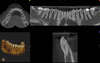

IMAGERIE 3D (CONE BEAM)

Le cabinet est équipé d'un appareil de radiographie panoramique

numérique qui fournit une représentation fidèle et en trois dimensions

de l’anatomie dentaire.

Il est également possible de réaliser un

examen radiographique complet (panoramique dentaire), et ce dès le

premier rendez-vous.

Le système bénéficie d’un champ d’examen

localisé qui produit des images de très hautes résolutions, que ce soit

en endodontie (pour mettre en évidence une infection dentaire ou

déterminer les causes d’un échec) ou en implantologie et chirurgie (pour

faire une planification des actes avec une plus grande précision), et

ce en respectant le principe ALARA (As Low As Reasonably Achievable).

Cette imagerie tri-dimensionnelle (3D) est effectuée avec une dose très

inférieure à celle d’un scanner médical, car il n’est pas nécessaire

d’irradier tout le complexe cranio-facial, et on limite le champ

d’examen à une partie de ce complexe, par exemple une seule mâchoire, ou

une zone concernant quelques dents.

Grâce à la possibilité

d’assemblage d’images que permet le logiciel, la totalité de la mâchoire

supérieure ou inférieure peut également être examinée.

De plus le logiciel permet de préfigurer avec précision le placement d’implants ou l’opportunité d’apposition osseuse, et ce, en quelques minutes.